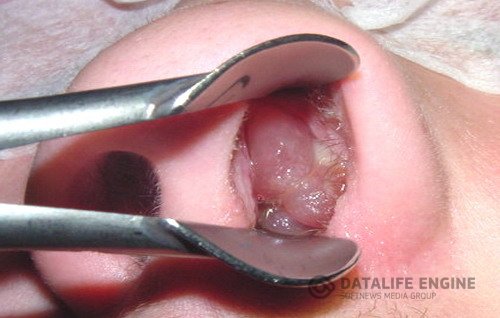

Полипы носа — довольно часто встречающееся осложнение заболеваний придаточных пазух носа. По своему внешнему строению (и клиническому течению) они напоминают доброкачественные опухоли (фибромы), а по механизму возникновения являются следствием серозно-катаральных воспалений придаточных пазух. Полипы имеют студенистую консистенцию и гладкую поверхность.

Цвет их колеблется от серого до желтовато-красного. Размеры зависят от времени возникновения. Величина и число полипов обычно сильно колеблются. Исходят полипы из среднего (редко из верхнего) носового хода. Если полипы образуются в придаточной пазухе носа, то он обычно направлен в сторону хоан (выходных отверстий носовых ходов в носоглотку).

Хоанальные полипы могут достигать больших размеров и закрывать вход в носоглотку. При носовых полипах больные обычно жалуются на заложенность носа, отсутствие носового дыхания, обильное количество слизистого или слизисто-гнойного отделяемого, головные боли, быструю утомляемость и понижение или отсутствие обоняния. Полипы могут быть односторонними и двусторонними. Лечение носовых полипов обычно оперативное. Операция не представляет особой сложности и часто проводится в условиях поликлиники.